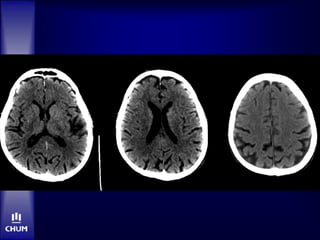

Angio-IRM: jour 3

IRM: jour 3

M. N. Jour 3 •Plus somnolent, mutique • Parésie jambe gauche